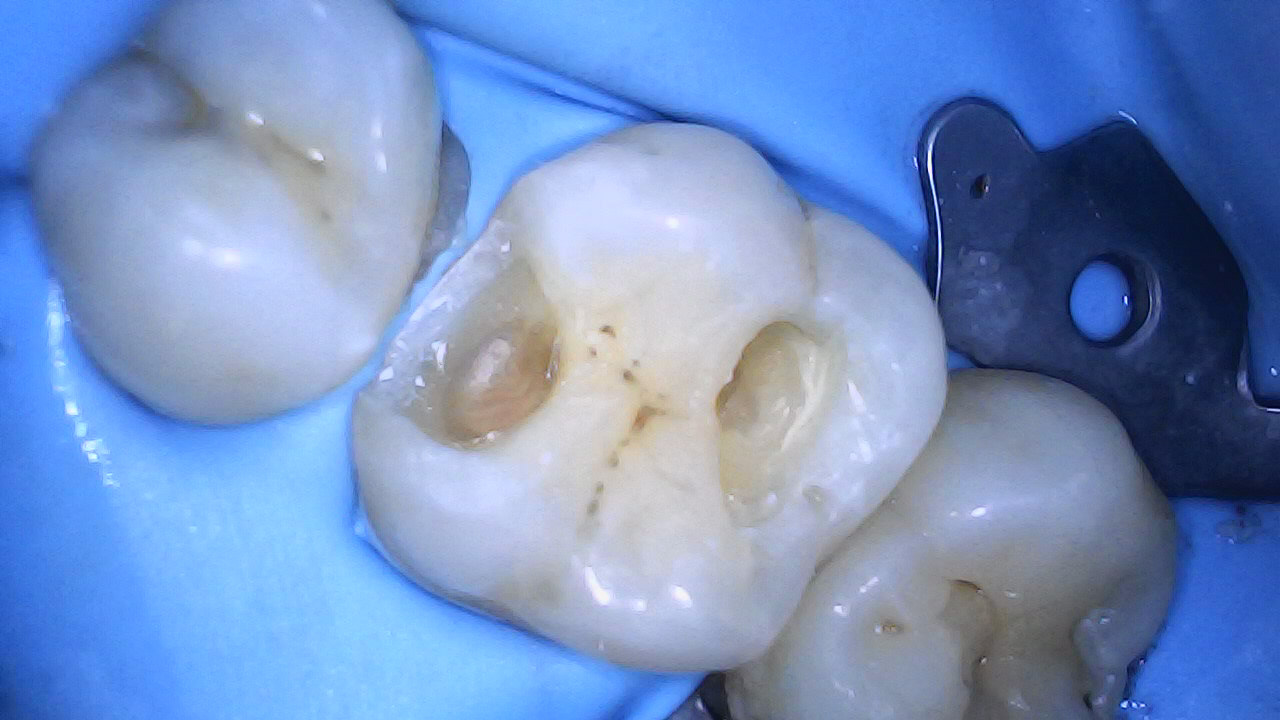

Cavity preps